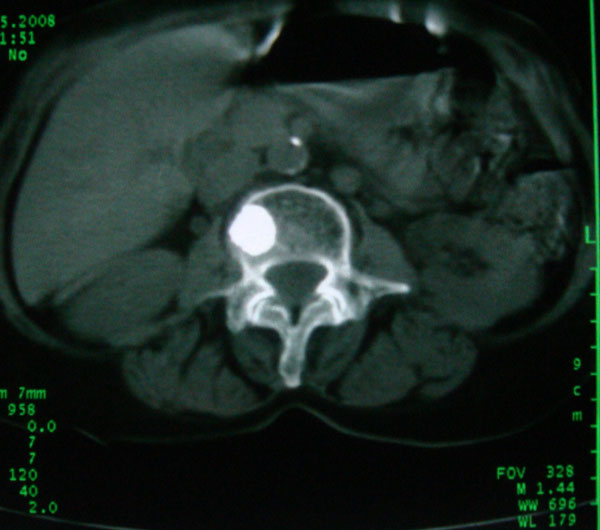

以下是引用卜一在2008-5-24 6:33:00的发言:[br]骨岛!建议定期复查!

以下是引用panyishengct在2008-5-23 23:19:00的发言:[br]骨岛,不排除成骨性转移瘤.

以下是引用pujunzhi在2008-5-24 1:02:00的发言:[br]支持2楼 骨岛,不排除成骨性转移瘤

以下是引用gaoshengjiang在2008-5-24 8:25:00的发言:[br]骨岛,不排除成骨性转移瘤. [br] [br]

以下是引用zjzjr在2008-5-24 14:55:00的发言:[br]骨岛!建议定期复查!